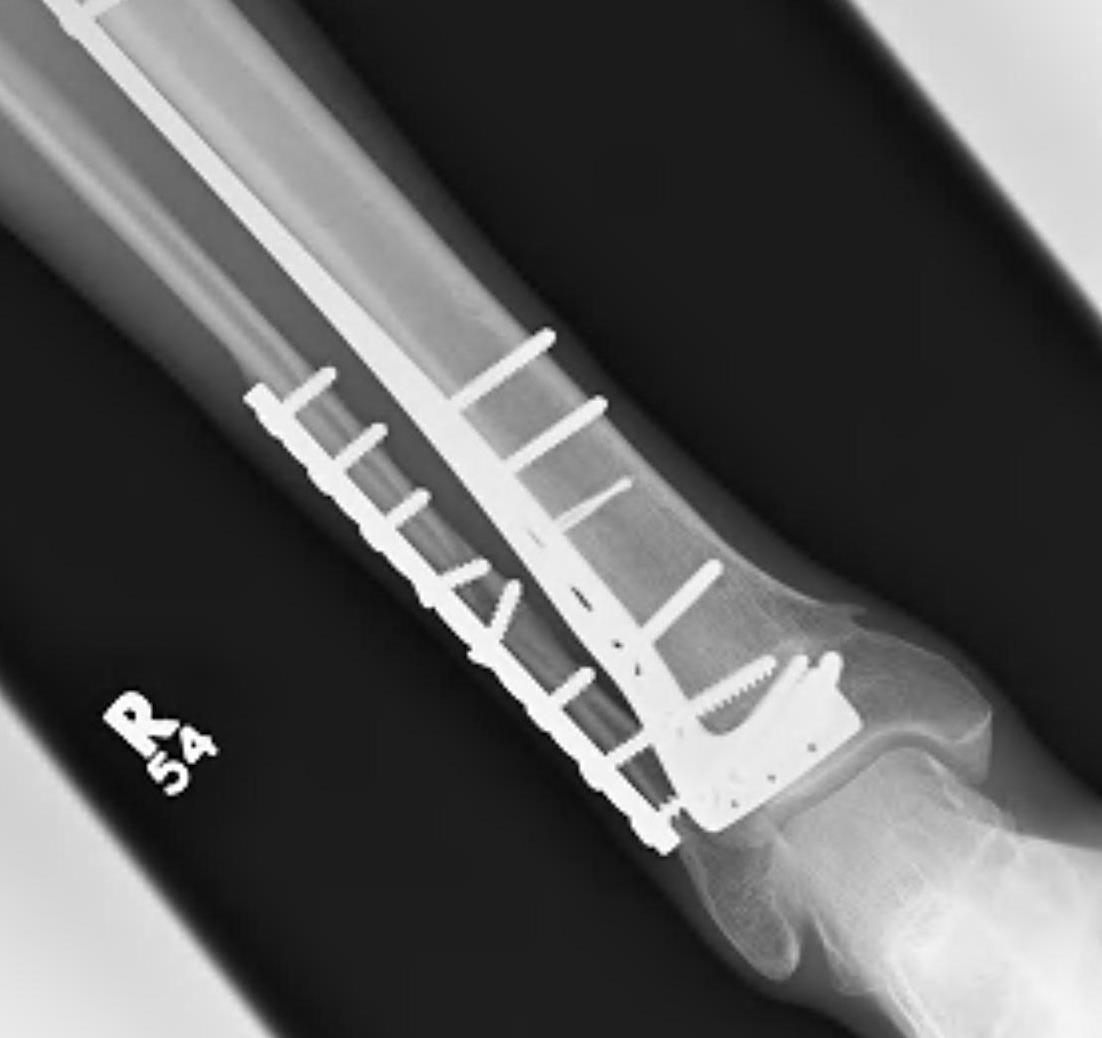

Intra-medullary Nail

Indications

- wounds / soft tissues not suitable to plate

- relatively stable

- sufficient distal bone

Design

Distal tibial nails

- multiple distal screws

- usually 2 medial-lateral and 1 AP

- most distal screw within 5 mm of end of nail

Technique

Consider semi-extended suprapatella nail

- easier to reduce fracture

- easier to get AP and lateral fluoroscopy

Most important is to centre guide wire over talus

- in lateral and AP

- use finger reduction tools and pass across fracture site to exact centre in AP and lateral

- bone reduction forceps

- blocking screws

- universal external fixation

- plate fibula